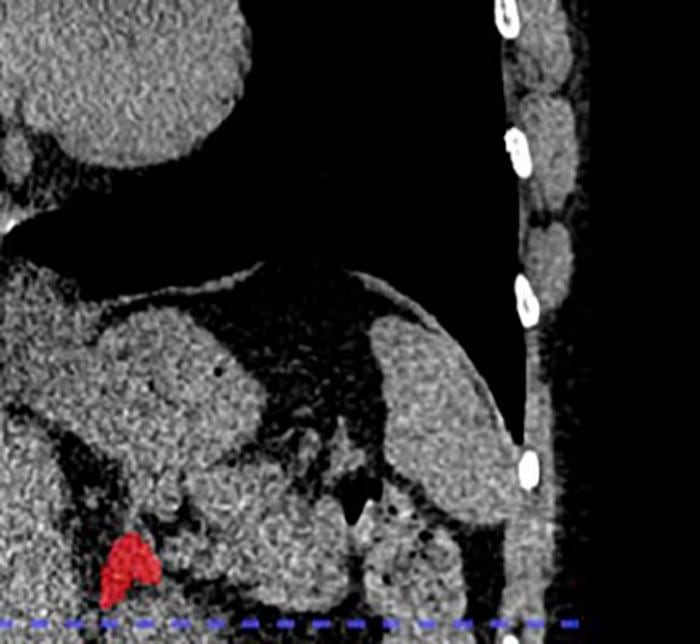

Y es que un equipo de investigadores liderado por la doctora Elena Ghotbi, del Johns Hopkins University School of Medicine, en Estados Unidos, entrenó un modelo de aprendizaje profundo para medir el volumen de las glándulas suprarrenales a partir de tomografías de tórax ya realizadas.

El indicador, llamado Índice de Volumen Suprarrenal (AVI, por sus siglas en inglés), se define como el volumen de las glándulas suprarrenales dividido por la estatura al cuadrado.

Este hallazgo representa una verdadera innovación clínica: por primera vez es posible “ver” el estrés crónico acumulado en el cuerpo mediante una imagen médica habitual, en lugar de depender únicamente de cuestionarios o mediciones puntuales de cortisol.